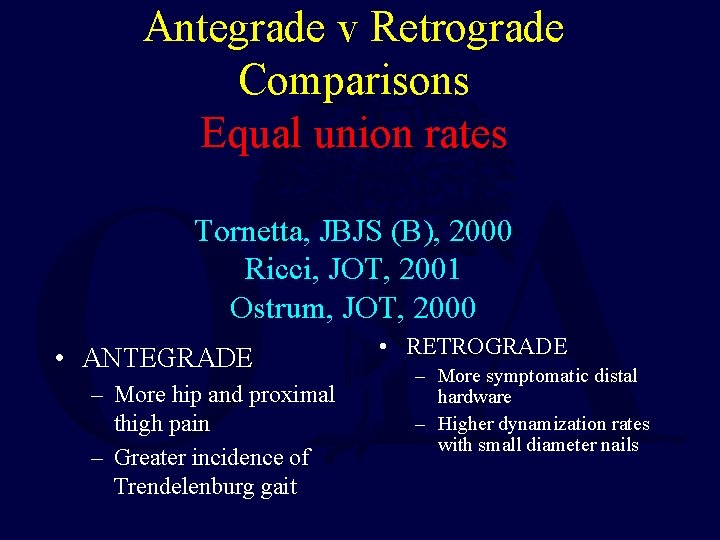

Antegrade v Retrograde Comparisons Equal union rates Tornetta, JBJS (B), 2000 Ricci, JOT, 2001 Ostrum, JOT, 2000 • ANTEGRADE – More hip and proximal thigh pain – Greater incidence of Trendelenburg gait • RETROGRADE – More symptomatic distal hardware – Higher dynamization rates with small diameter nails